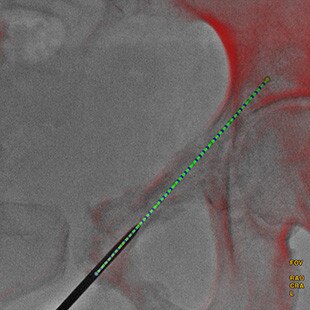

Guider